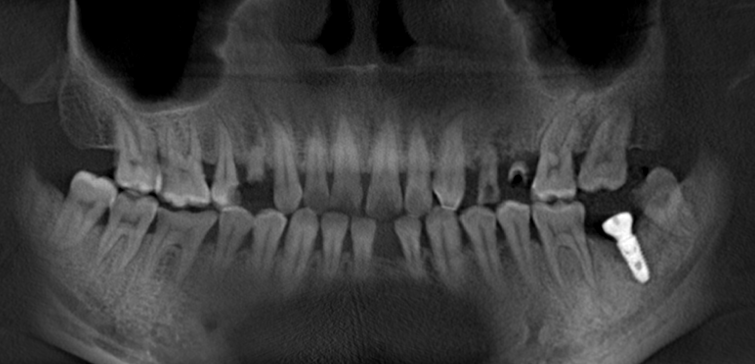

种植后CT

种植牙关键之处在于医生的技术与经验,种植体植入的方向、位置、角度、深度等,都有严格的要求,经验丰富的种植医师可以将种植体植入到理想的位置,手术成功率更高、安全性更高,效果也更好。